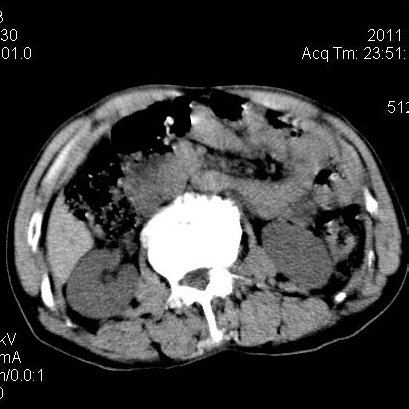

肝左叶发育异常

男性,55岁,骑摩托车摔倒后入院,自述右上腹疼痛

[backcolor=#FF0000]第一次诊断的时候也是这么肯定,可是床旁超声检查并没有发现明显异常,而且患者的一般症状都良好。还好临床只是保守治疗,没有立即手术,第二次复查的时候没有一点变化,又做了MRI检查,没有血肿,

这是一例肝左叶发育异常的,很个性吧~[/backcolor]